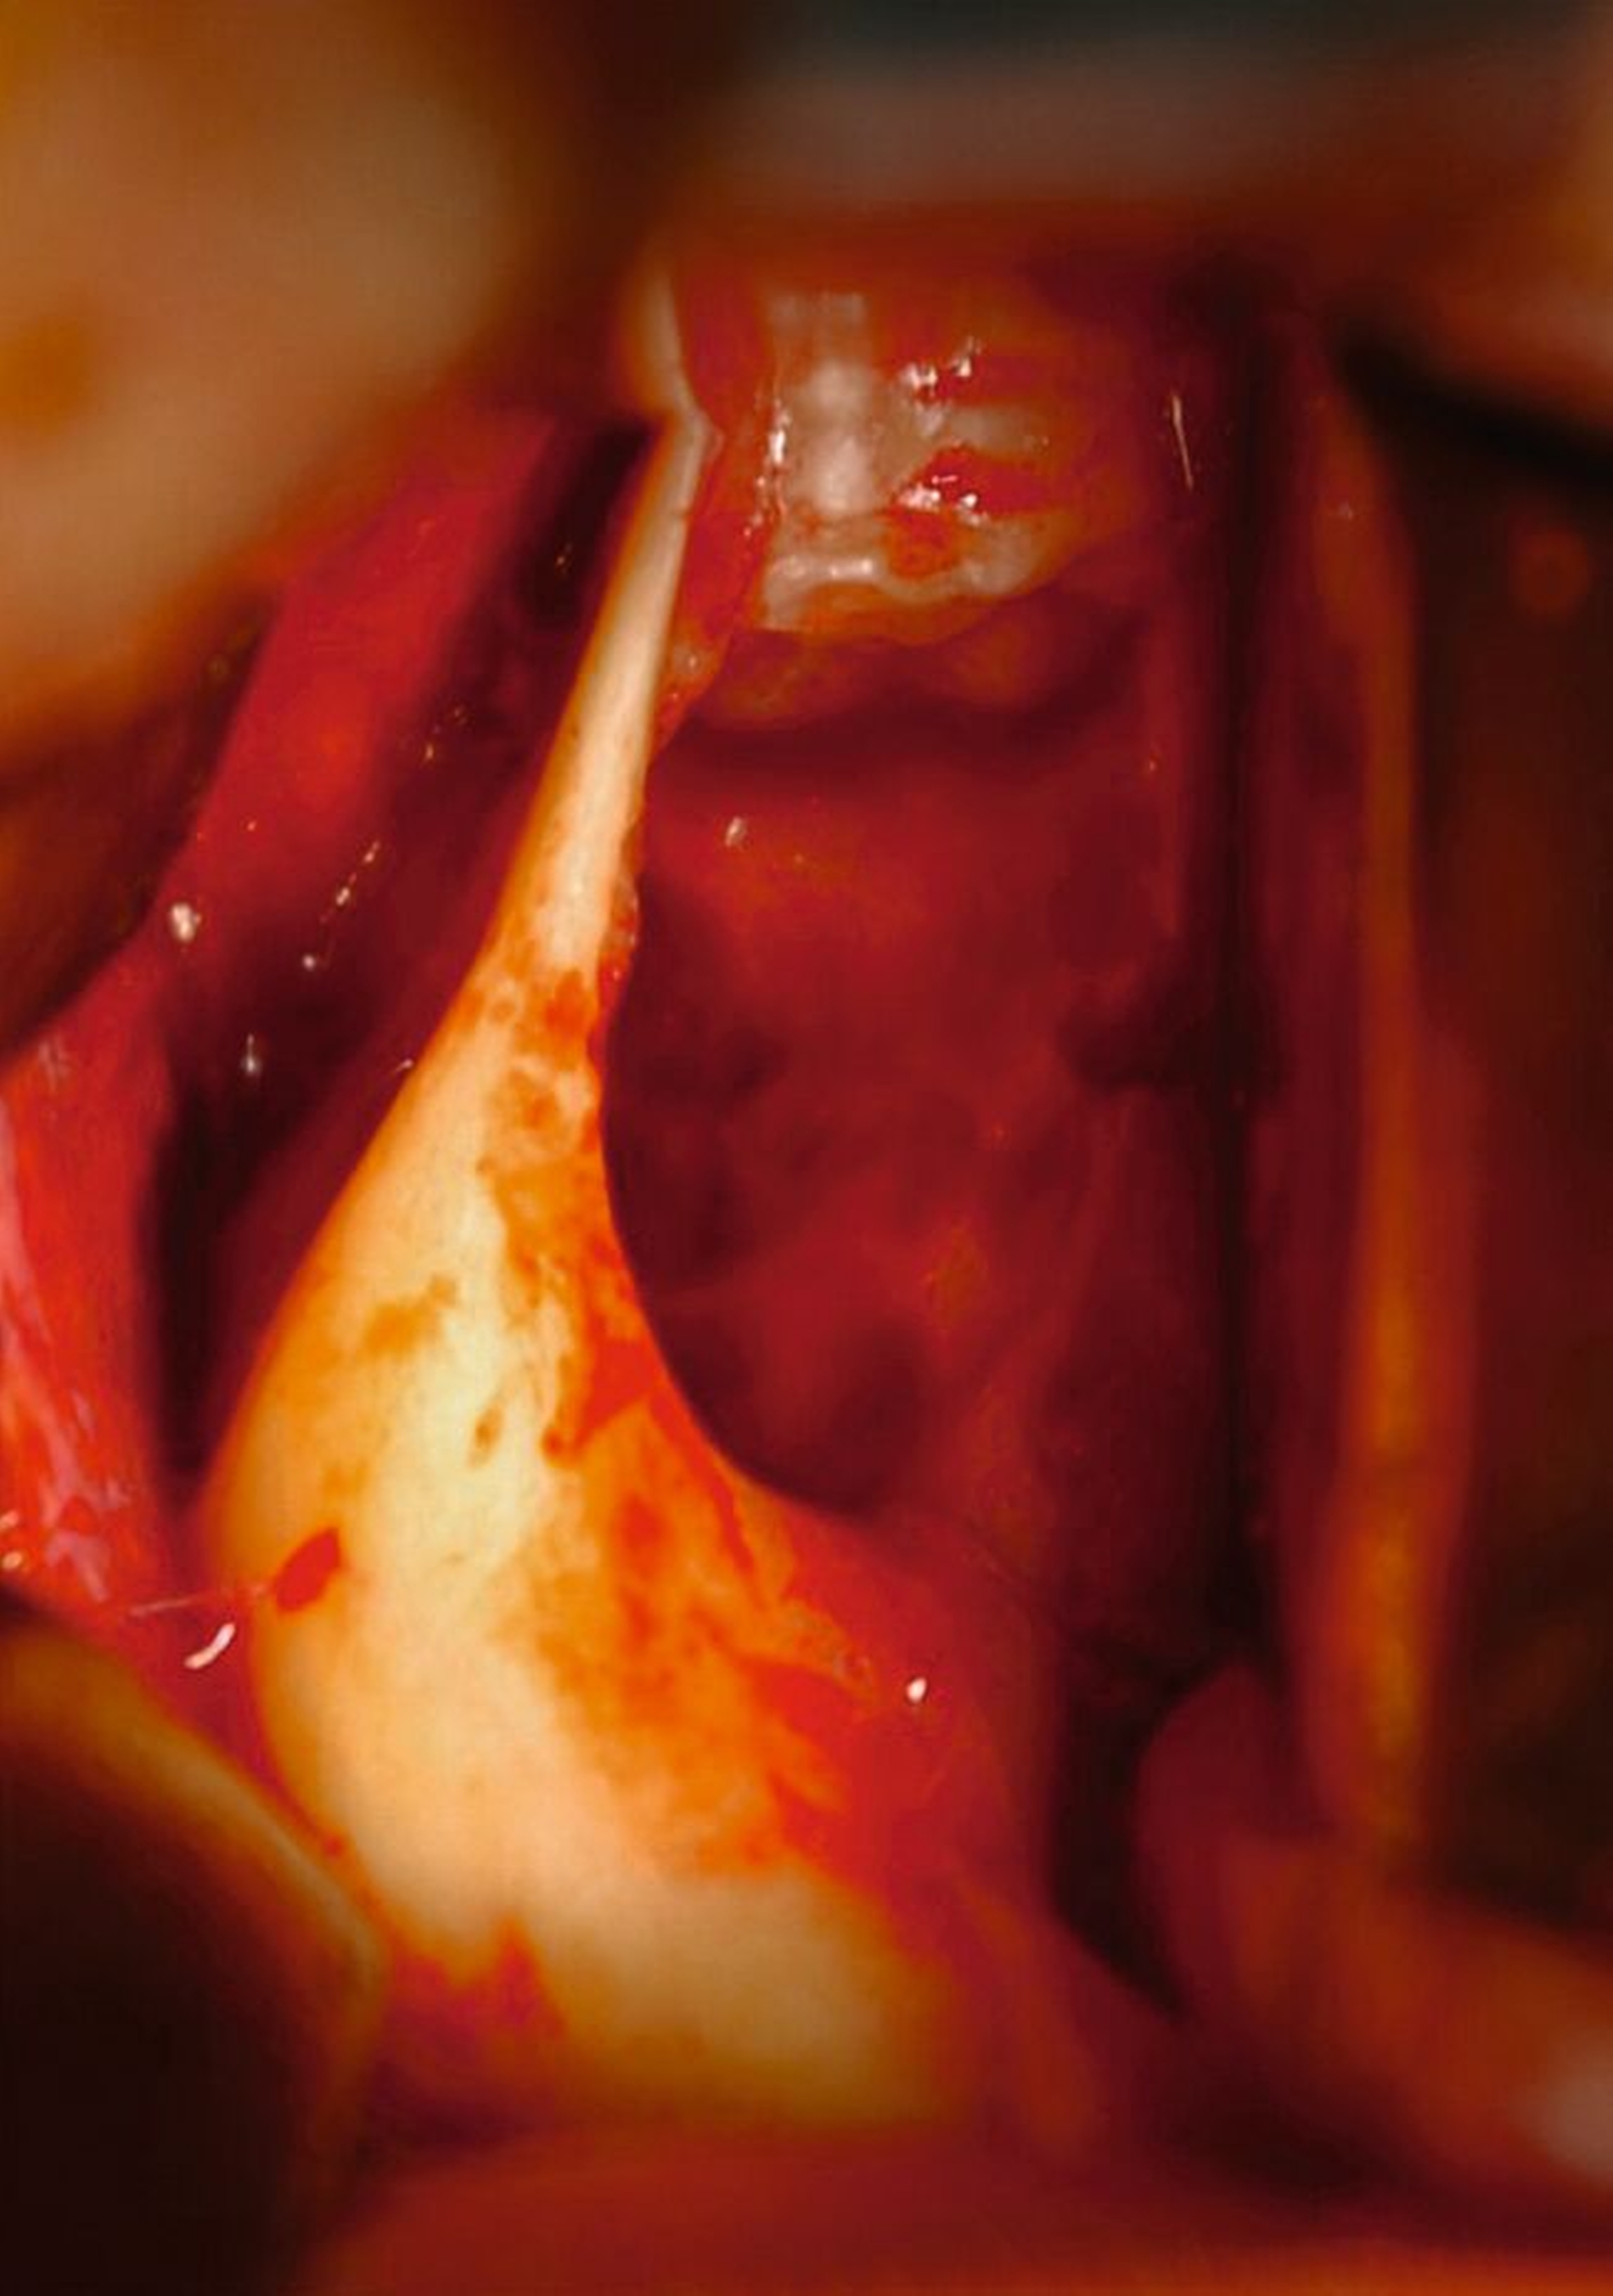

Nach Lokalbehandlung der akuten Entzündung erfolgt in nasaler Intubationsnarkose (ambulantes MedizinZentrum Lichtenberg, Sana-Klinikum Berlin) die Entfernung des kariösen retinierten Zahns mit Ausräumung der Entzündung. Der blande, hochretinierte Distomolar wird ebenso wie die Zähne der Gegenseite belassen, die Resektionshöhle im rechten Kieferwinkel mit Beckenkammspongiosa verfüllt.

Im anterioren Bereich des Unterkiefers erfolgt eine vestibulo-crestale Verschalung durch schraubenfixierte (Osteosyntheseschrauben Mini 2,0, KLS Martin, Tuttlingen) Beckenkammspäne.